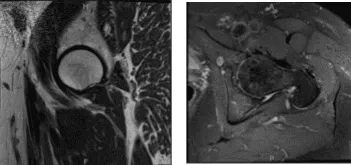

He visited after a week for a follow up and presented the results of his MRI and showed mild left hip degenerative change with insertional gluteus Medius tendinosis and partial tearing with mild greater bursitis. Mild RIGHT hip degenerative change. Insertional gluteus minimus tendinosis and partial tearing with mild greater trochanteric bursitis.

MRI-3T left hip non-contrast

MRI-3T Right hip non-contrast